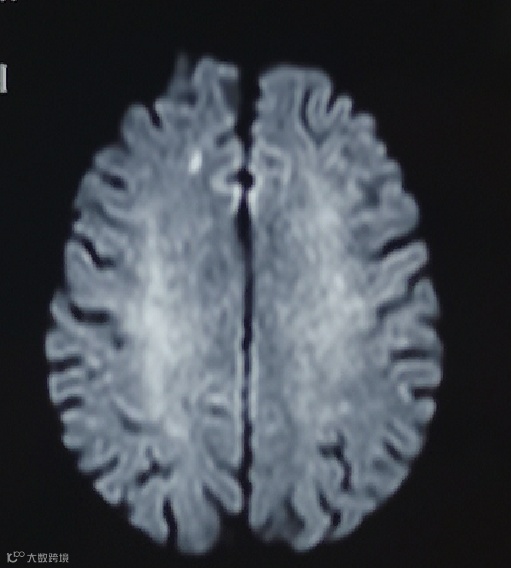

患者取仰卧位,全麻下右侧股动脉穿刺置入8F血管鞘,全身肝素化。5F单弯在泥鳅导丝引导下行全脑血管造影,可见基底动脉尖动脉瘤,左椎优势供血伴起始处迂曲,左侧非胚胎型大脑后动脉(图3,4)。

图3

图4